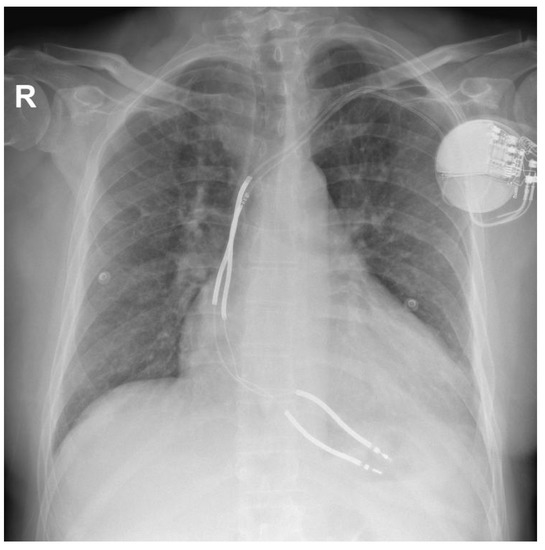

At the time of admission to our department, the patient was asymptomatic. The ECG showed a sinus rhythm with left bundle-branch block. A chest X-ray revealed an increased cardiothoracic ratio, a pulse-generator ICD placed subcutaneously in the left subclavian area, and two dual-coil defibrillation leads in the apex of the right ventricle (Figure 2).

Figure 2. Chest X-ray at the time of admission at the hospital.